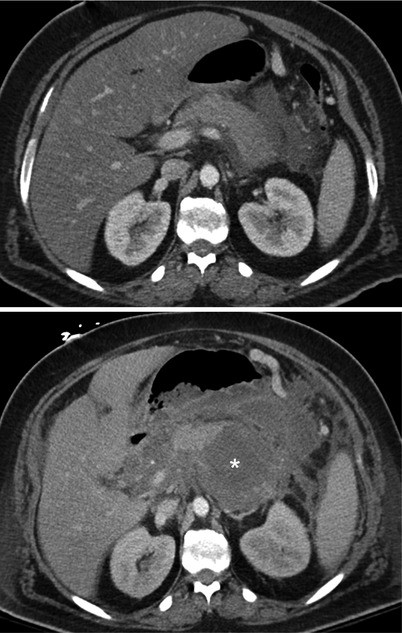

Pelvic Free Fluid In Patient With Diffuse Fluid And No Distant Air Download Scientific Diagram

Pelvic Free Fluid In Patient With Diffuse Fluid And No Distant Air Download Scientific Diagram from www.researchgate.net